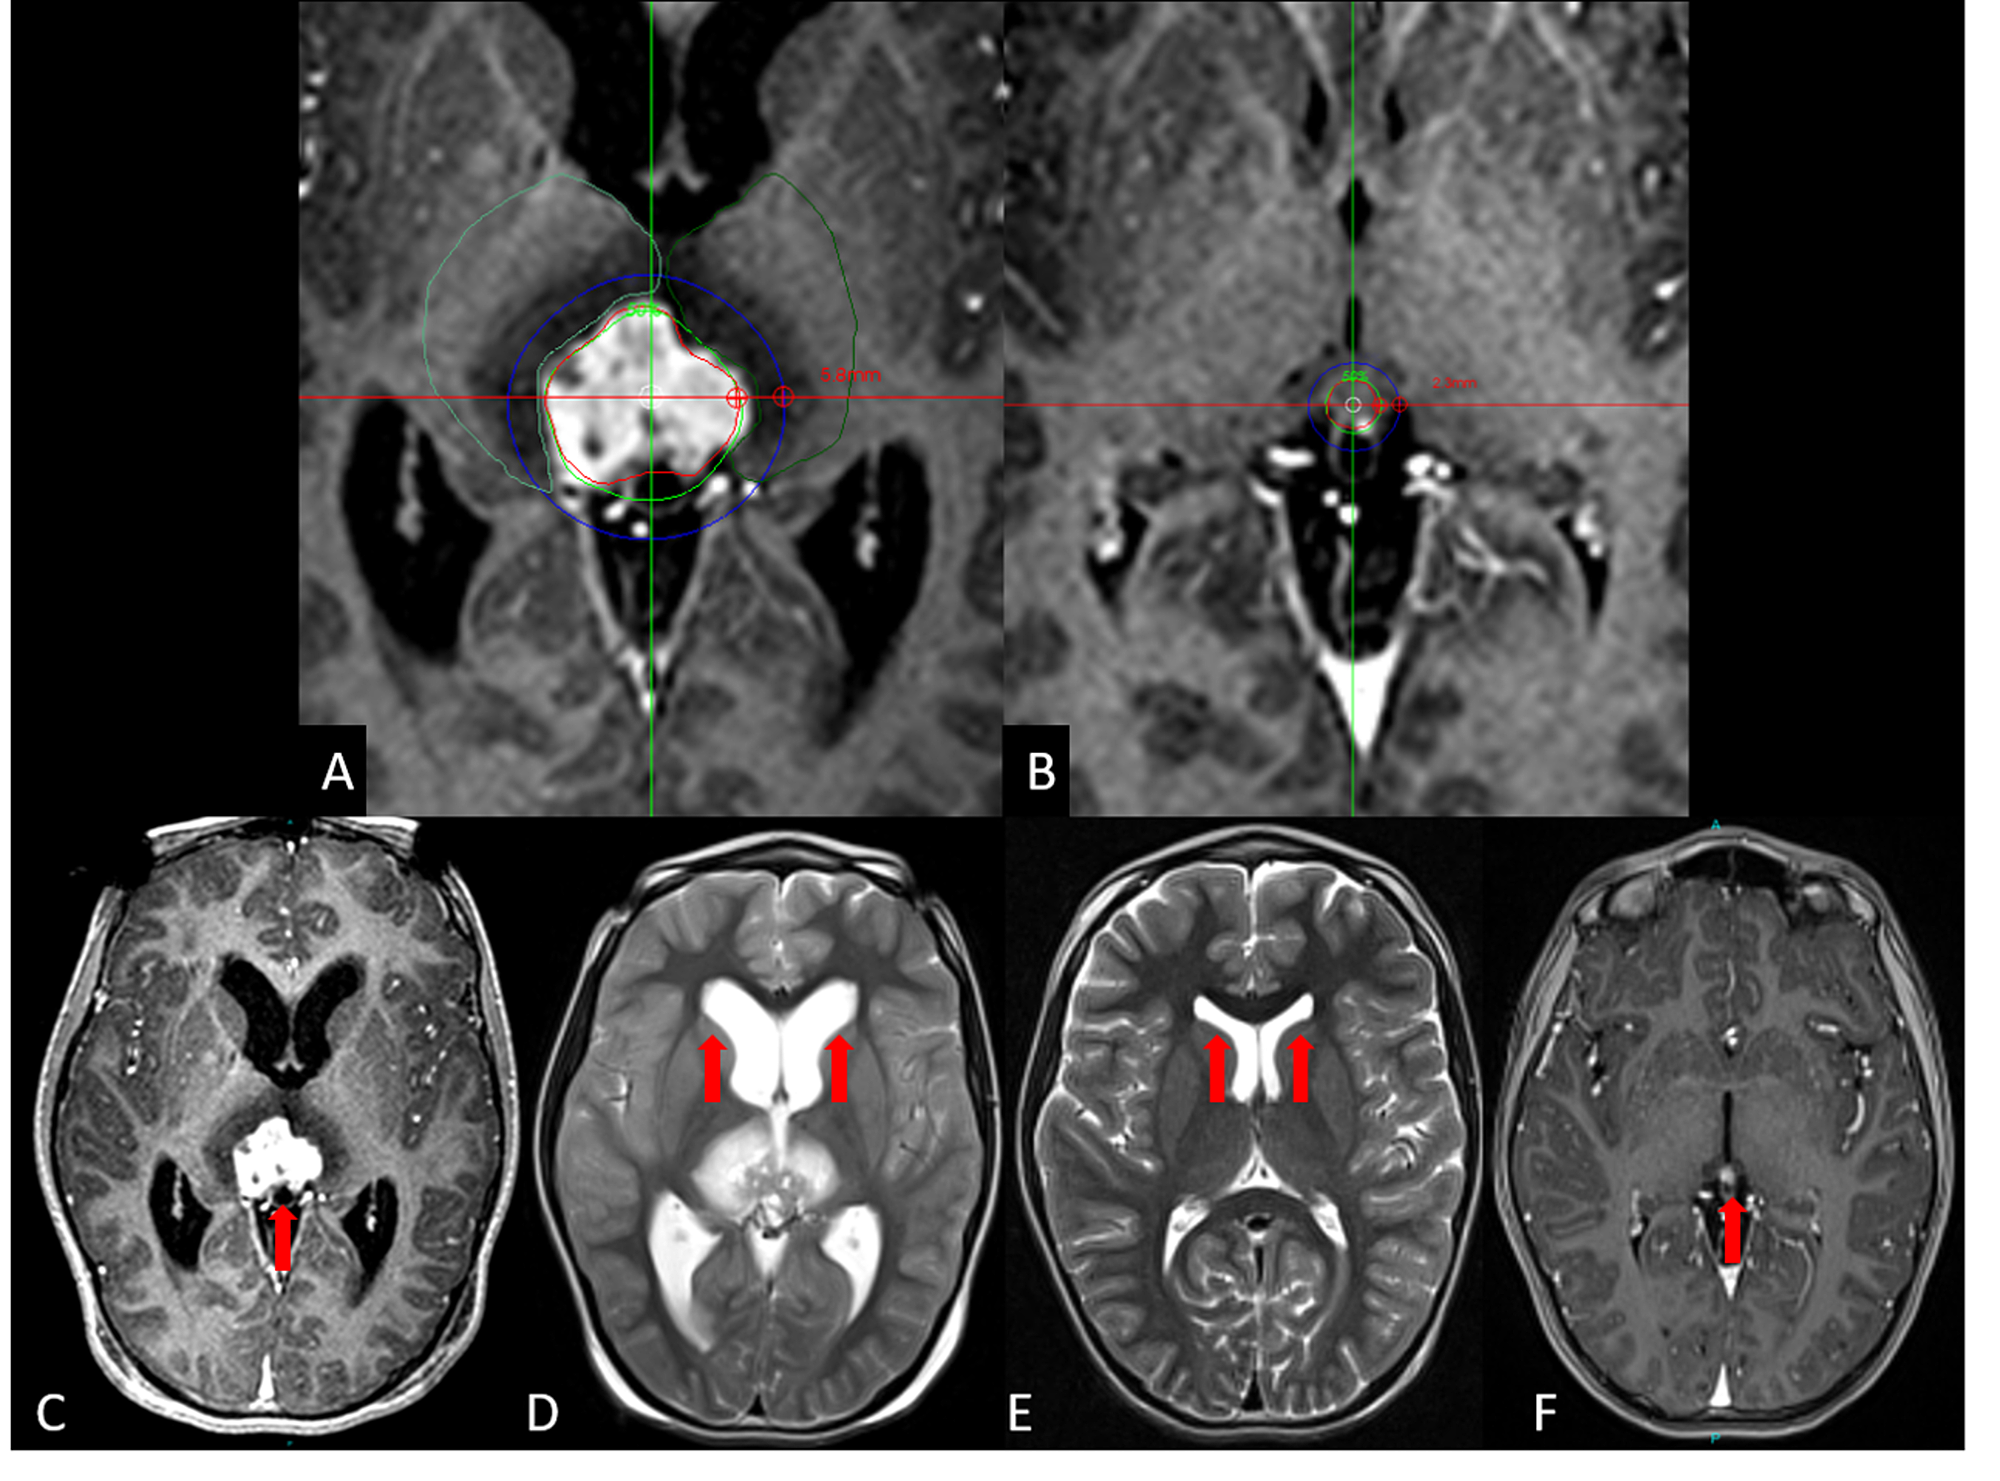

From www.researchgate.net

Top panel Patient with right cerebellar lesion before stereotactic Radiosurgery Brain Lesions Stereotactic radiosurgery should be considered as a valid adjunctive therapy to supportive palliative care for some patients with brain metastases when it. (a) srs alone for 5 to 15 lesions and. There are different types of technology used in. Stereotactic radiosurgery targets brain abnormalities or the area of your brain that shows symptoms. Find out whether you might be a. Radiosurgery Brain Lesions.